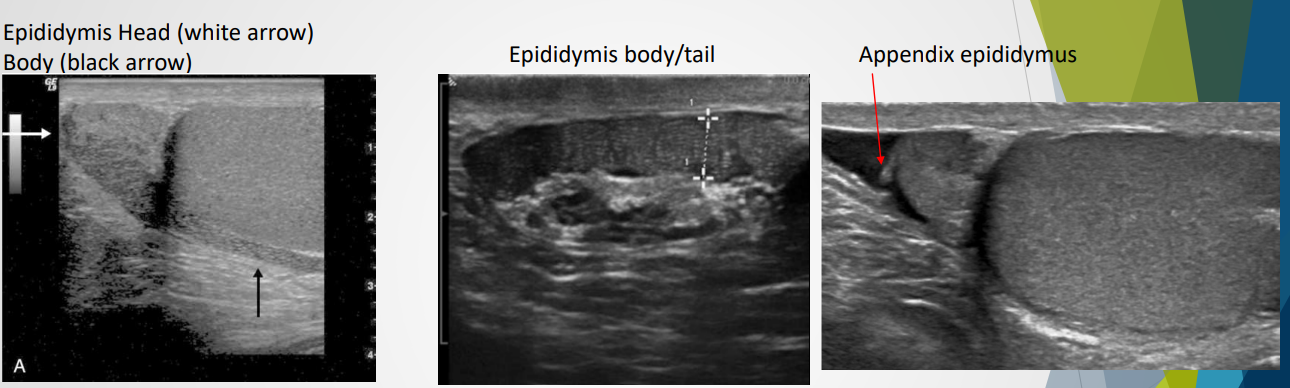

Epididymis:

Size: 6-7 cm, structure divided into head, body, and tail.

Begins superiorly and runs posterolateral to the testes

Head: superior to upper of testes, contains 10 - 15 efferent ductucles from the rete testis which forms a single duct in body and tail. This duct becomes the vas deferens and moves into the spermatic cord

Body: smaller than the head and follows the posterorlateral aspect of the testes from upper to lower pole

Tail: slightly larger than the body and sits posterior to the lower portion of testes

Appendix of the epididymis: small protuberance from the head

Ultrasound appearance: similiar or hypoechoic to testes; coarse echotexture